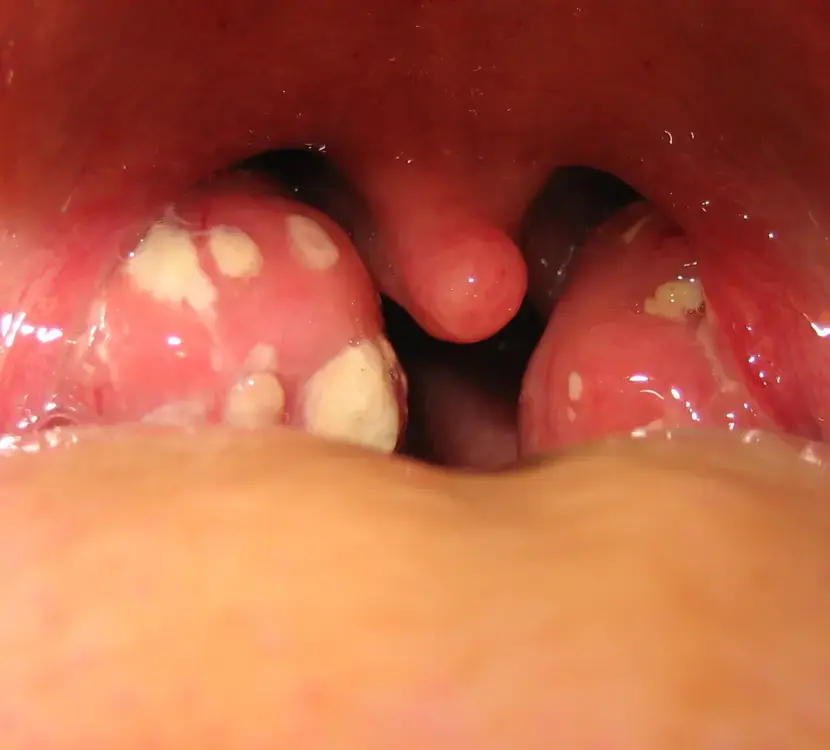

La amigdalitis es la inflamación de las amígdalas, masas de tejido linfoide que se localizan en la parte posterior de la garganta y son parte del sistema inmunológico que ayudan en la protección contra infecciones.

Esta enfermedad se manifiesta con dolor de garganta, fiebre, malestar general e inflamación de los ganglios del cuello, la misma puede ser causada por virus y bacterias.

La fiebre reumática se manifiesta con una variedad de síntomas que dependen del órgano afectado y que pueden evolucionar con el tiempo. Inicialmente, la infección por estreptococo se presenta como una faringoamigdalitis, caracterizada por fiebre repentina, dolor de garganta, dificultad para tragar, dolor de cabeza, náuseas y vómitos.